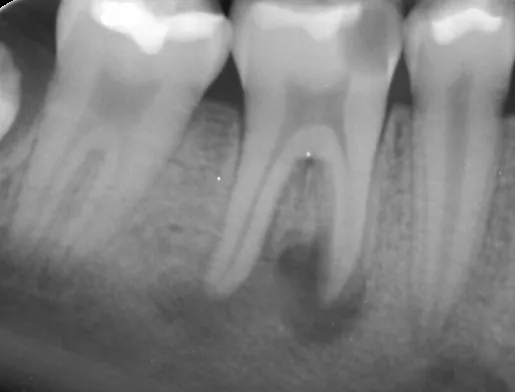

The Endodontic treatments in our clinic are done by Dr Maria Moukarzel.

Endodontics is the study, prevention, diagnosis, and treatment of diseases associated with the roots of the teeth. Endodontic services aim to save the patient’s natural teeth by restoring dental health and function.